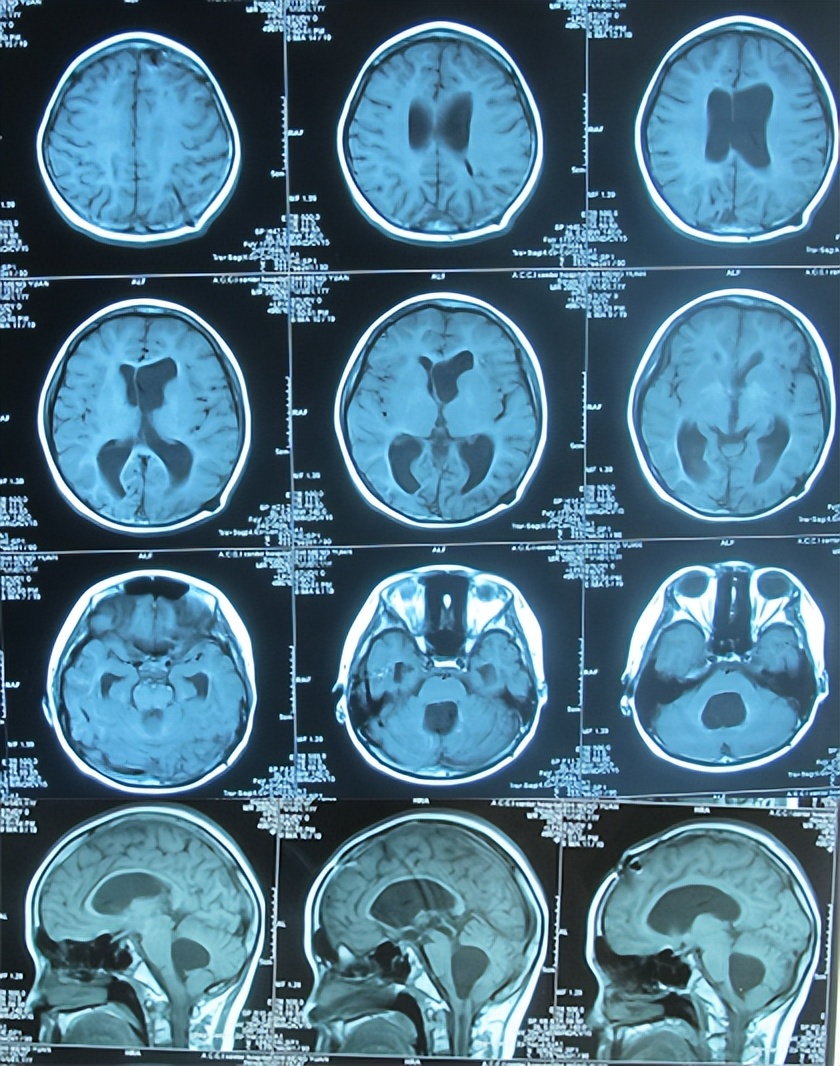

出院后1年零4个月即2012年7月15日复查。复查时:已完全恢复正常健康的状态,激素性面部也完全消失,并向医护人员展示了学习优秀的奖状,也这说明了其智力也完全回到了正常健康水平(图-23);虽此时复查颅脑核磁虽显示第四脑室扩大、感染性小脑扁桃体下疝合并脊髓空洞的异常后遗症表现(图-24);但患儿目前状态一切正常,因此建议继续观察定期复查。

图-24:2012年7月15日头颅核磁